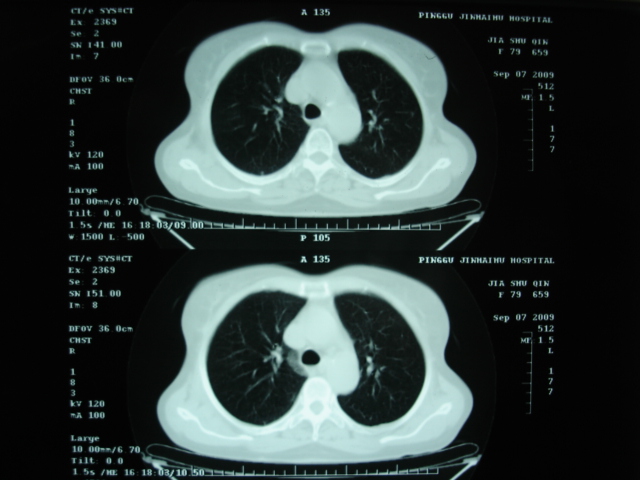

以下是引用卜一在2009-9-7 19:51:00的发言:[br][br] 1 左侧胸内甲状腺占位-多考虑甲状腺腺瘤! 2、左肺门占位-建议增强扫描以便明确性质。 3 慢支并感染! [br]

以下是引用shibing在2009-9-7 20:40:00的发言:[br]左侧胸内甲状腺占位-多考虑甲状腺腺瘤! 2、左肺门占位-建议增强扫描以便明确性质。 3 慢支并感染! [br]